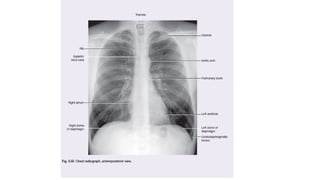

B) y C) muestran radiografía del tórax en espiración completa (B) y en la inspiración

pulmones en espiración plena. Note la diferencia en el volumen intratorácico